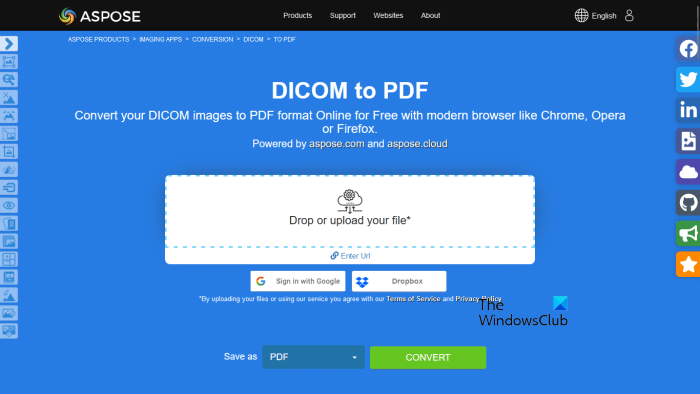

4] Aspose

Aspose is another free online tool to convert DICOM images into PDF format. It is a batch DICOM to PDF converter tool. Hence, you can use it to convert multiple DICOM images into PDF files at once. You can upload a DICOM image to its server from your computer, Dropbox, or by entering a URL.

After uploading the DICOM files, click on the convert button. After the conversion process gets completed, download the converted files on your computer. If you carry out a batch conversion, the downloaded files will be downloaded in zip format. Hence, you have to extract them.

Visit aspose.app to carry out batch DISOM to PDF conversion.